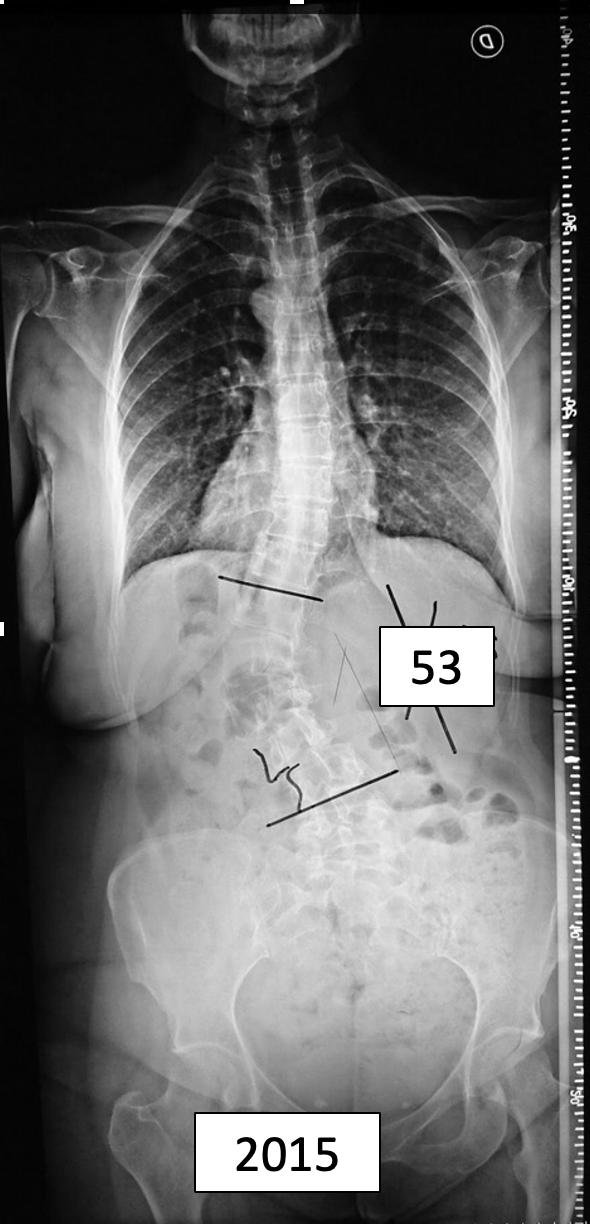

Marcela

DR. PABLO FIORILLO – Mat. 17034

Cirujano de Columna

Especialista en Escoliosis Pediatricos y Adultos